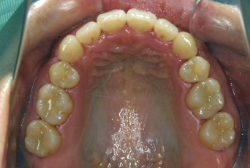

「隙間を閉じたい」という主訴で来院したケースです。診断の結果、「空隙歯列弓+軽度叢生」と判明しましたが、この方の場合は上は隙がある、つまりスペースが余っているのに対して、下は軽度の凸凹がある、つまりスペースが足りないと言う状態でした。

通常、凸凹の症状の場合は、小臼歯を抜歯させていただくのですが、この方の場合は凸凹も軽度で親知らずもないため、非抜歯で対応することになりました。マルチブラケット装置にて治療を開始し、治療期間は11ヶ月でした。治療後は正中の空隙が閉鎖されただけでなく、下の凸凹と下の歯並びの形態そのものが大幅に改善されました。もちろん噛み合わせ的にも正しい状態が確立しています。